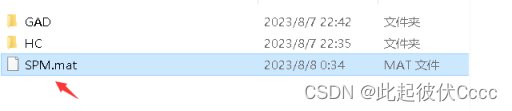

4.点击RUN运行后在之前设置的输出路径下生成.mat文件